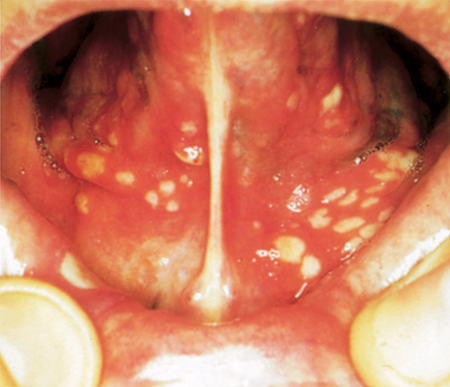

Finally, the herpetiform canker sores are considered to be the most severe, since they are composed of dozens of minor canker sores that are clustered together, often creating a single large ulcer. These will heal within a month and usually, do not scar.(11*)